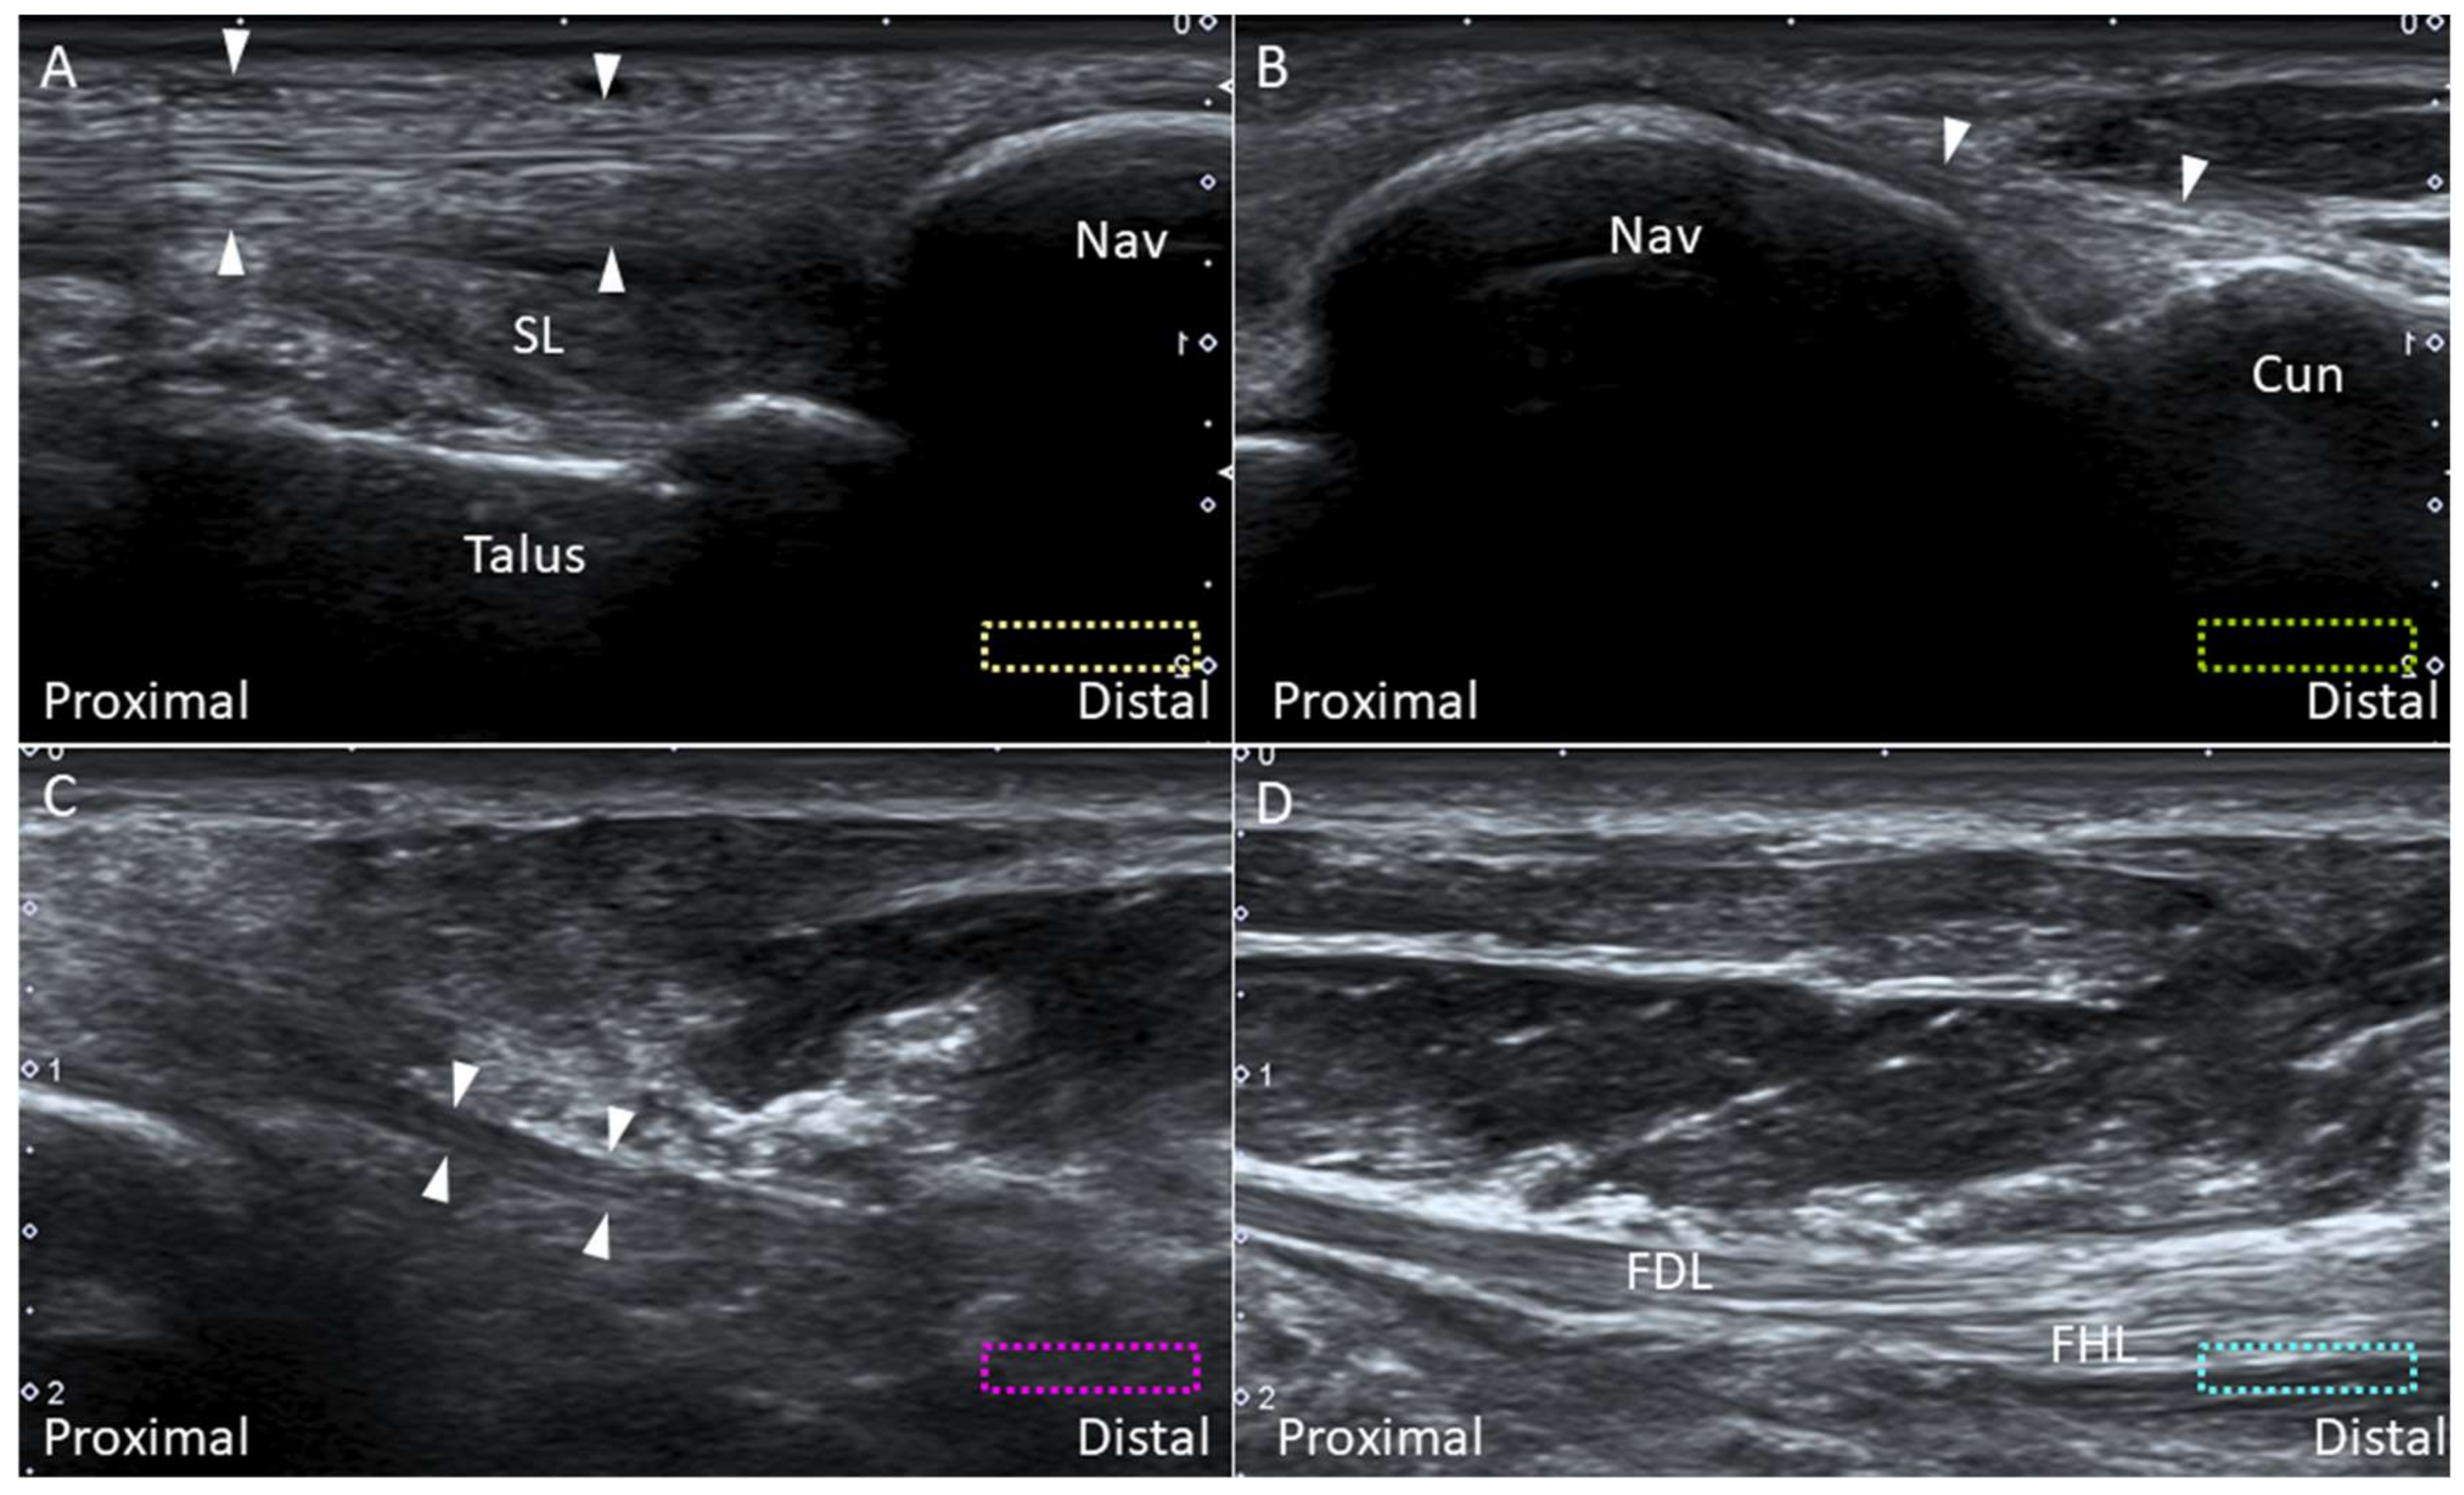

2.8. Spring Ligament

2.8.1. Anatomy

2.8.2. Scanning Technique

2.8.3. Clinical Relevance

2.7. Deltoid Ligament

2.7.1. Anatomy

2.7.2. Scanning Technique

2.7.3. Clinical Relevance

5.1. Medial Plantar Nerve (Over the Knot of Henry)

5.1.1. Anatomy

5.1.2. Scanning Technique

5.1.3. Clinical Relevance

5.2. Baxter Nerve

5.2.1. Anatomy

5.2.2. Scanning Technique

5.2.3. Clinical Relevance